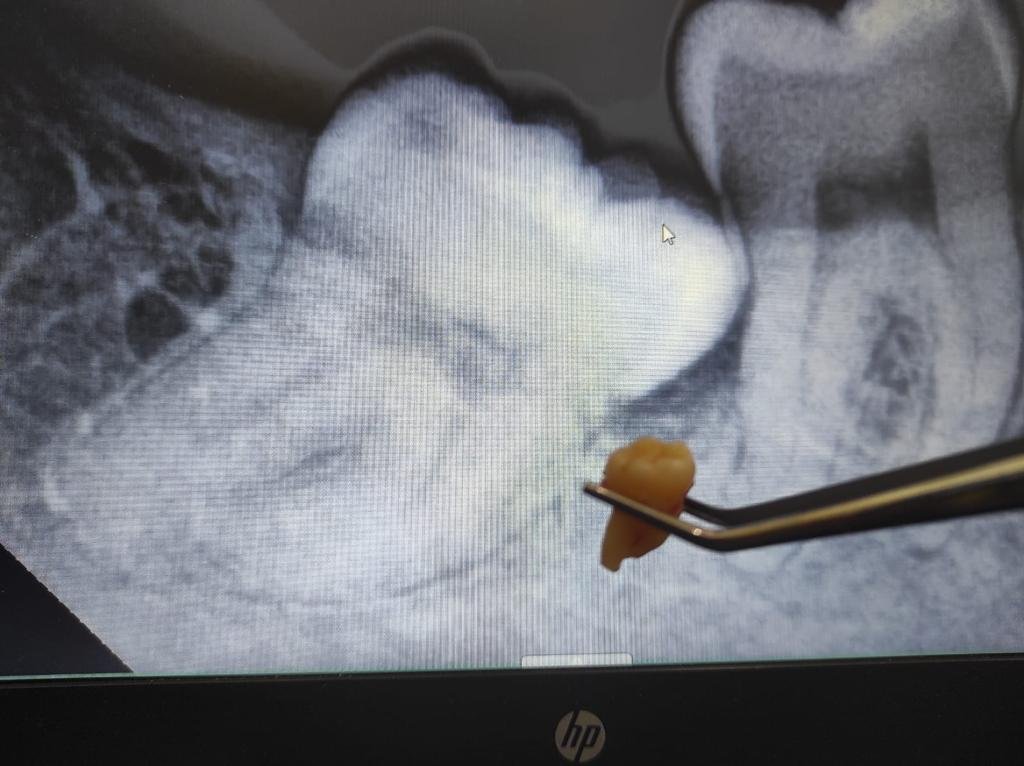

ciri ciri impaksi gigi dan perlu operasi gigi bungsu

Kapan Odontektomi Dibutuhkan?

Pasien biasanya membutuhkan odontektomi dalam kondisi berikut:

• Gigi bungsu impaksi, tumbuh tidak sempurna dan menekan gigi di sebelahnya.

• Infeksi gusi berulang (perikoronitis) karena gigi hanya muncul sebagian.

• Kerusakan gigi sebelahnya akibat dorongan dari gigi bungsu.

• Kista atau tumor rahang yang berkembang di sekitar gigi bungsu.

• Rencana ortodonti (behel) yang mengharuskan dokter menciptakan ruang tambahan pada rahang.